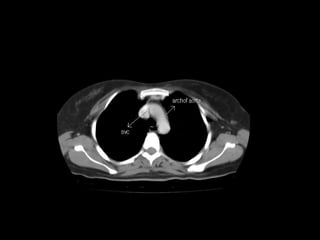

Radiographers use medical imaging equipment like X-rays and MRIs to produce images of patients' internal structures and organs. They are responsible for positioning patients, operating scanning machines, and ensuring quality images. Radiographers must have strong attention to detail, excellent communication skills, and the ability to work well under pressure to accurately capture anatomical features and diagnose any abnormalities.